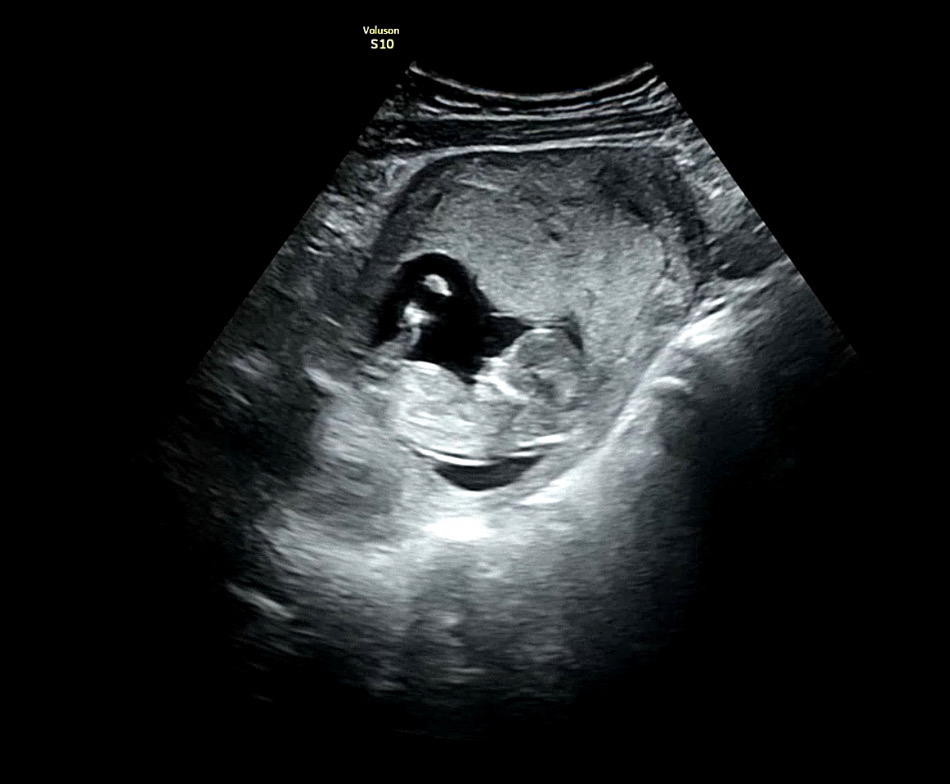

12주 1일차 각도법 문의합니당

각도법이 보이는 각도인지 애매하긴하지만 궁금해서 남겨봅니다 :) 참견 부탁드려요옹...❤️